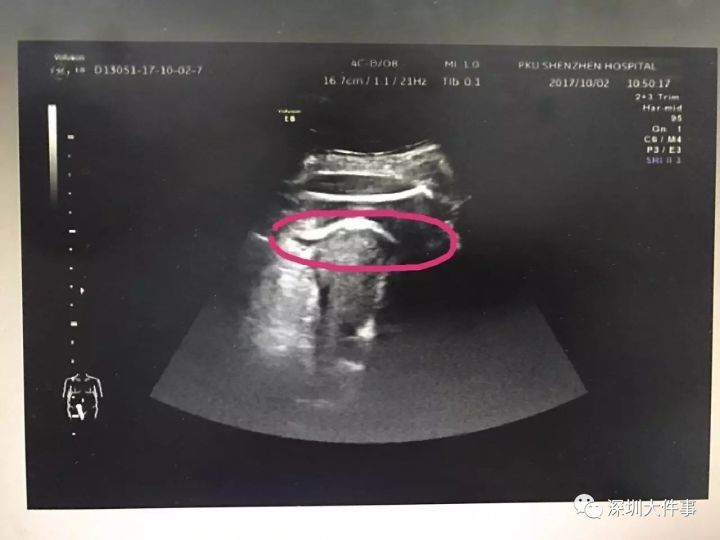

医生初步怀疑患者子宫破裂,当即安排做了B超。检查发现,胎儿的一条腿“踢破”了子宫,进入了腹腔,大腿根正卡在子宫壁上!医生追问患者病史,原来张女士2016年做过子宫肌瘤剔除术,术后半年就怀孕了。不到2分钟B超检查,仅凭有限病史,医生快速作出诊断:高度怀疑为疤痕子宫破裂。

当时,孕妇面临失血性休克和感染双重威胁,胎儿也随时有生命危险。从确诊病情到送手术室,前后只用了不到5分钟。对于张女士和腹中胎儿来说,时间就是生命。在妇产科副主任医师章蕾指导下,张艳萍和钟世林值班医生第一时间施行了手术,不到10分钟,就将胎儿顺利剖出。胎儿出生后生命体征平稳,逃过一劫。